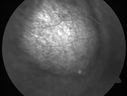

Choroidal Metastases - Both Eyes - Exudative Retinal Detachmentvu 1412 fois58-year-old man smoke a pack of cigarettes a day. He has had some ribcage pain for about the last two weeks. He also had a sinus infection for about two weeks, and he has also had hazy vision on the superior visual field in the left eye for about the last two weeks. vision is 20/25 in both eyes

Choroidal Metastases - Both Eyes - Exudative Retinal Detachmentvu 907 fois58-year-old man smoke a pack of cigarettes a day. He has had some ribcage pain for about the last two weeks. He also had a sinus infection for about two weeks, and he has also had hazy vision on the superior visual field in the left eye for about the last two weeks. vision is 20/25 in both eyes

Choroidal Metastases - Both Eyes - Exudative Retinal Detachmentvu 823 fois58-year-old man smoke a pack of cigarettes a day. He has had some ribcage pain for about the last two weeks. He also had a sinus infection for about two weeks, and he has also had hazy vision on the superior visual field in the left eye for about the last two weeks. vision is 20/25 in both eyes

Choroidal Metastases - Both Eyes - Exudative Retinal Detachmentvu 796 fois58-year-old man smoke a pack of cigarettes a day. He has had some ribcage pain for about the last two weeks. He also had a sinus infection for about two weeks, and he has also had hazy vision on the superior visual field in the left eye for about the last two weeks. vision is 20/25 in both eyes